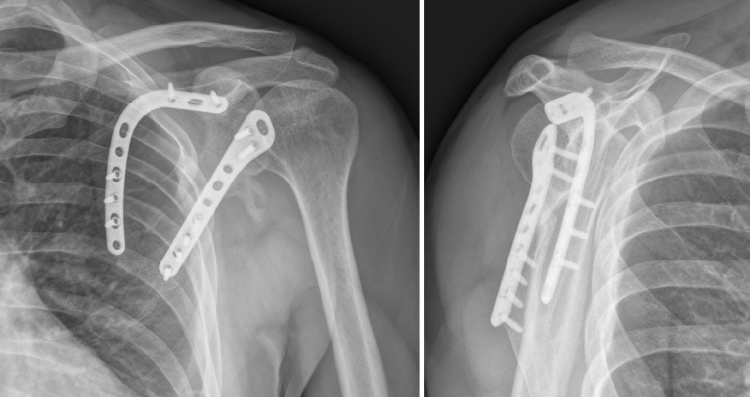

Una vez colocados los tornillos, comprobamos la correcta reducción de la fractura mediante control fluoroscópico. Dejamos un drenaje aspirativo subcutáneo, que retiraríamos a las 24 horas de la cirugía, momento en el que hacemos el primer control radiográfico. El paciente sale del quirófano con un cabestrillo que mantenemos durante 4 semanas, en las cuales le permitimos iniciar ejercicios de péndulo. Entre la segunda y la cuarta semana tras la cirugía el paciente comienza a realizar ejercicios pasivos en todo el rango de movimiento. A partir de la cuarta semana, son permitidos los ejercicios activo-asistidos hasta la sexta semana, momento en el que se le permite realizar ejercicios activos, una vez que se espera encontrar signos de consolidación clínicos y radiológicos.

En el control de la cuarta semana postoperatoria se observaron signos de consolidación radiográfica y ausencia de dolor sin medicación analgésica (escala visual analógica = 0). Al final del seguimiento (7 meses tras el tratamiento quirúrgico) el paciente conseguía una movilidad activa consistente en 120° de flexión y de abducción, una rotación interna suficiente para tocar con el pulgar su espalda a nivel de la vértebra T12 y una rotación externa en la que conseguía llevarse la mano a la nuca sin antepulsar el codo. Se evidenció, no obstante, una leve pérdida de fuerza con respecto al hombro contralateral. Tras 112 días de baja laboral desde el día del accidente, el paciente fue reincorporado a su puesto de trabajo laboral sin secuelas reseñables y con el control radiográfico que se muestra en la Figura 11.

Figura 11. Control radiográfico al final del seguimiento (7.º mes postoperatorio).